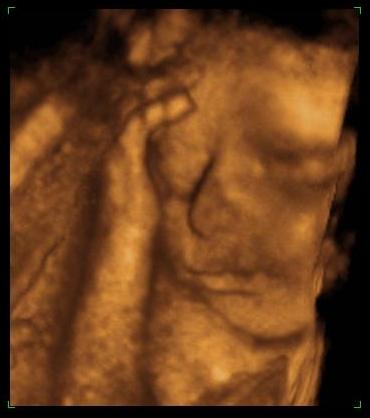

Bence 18 hetesen